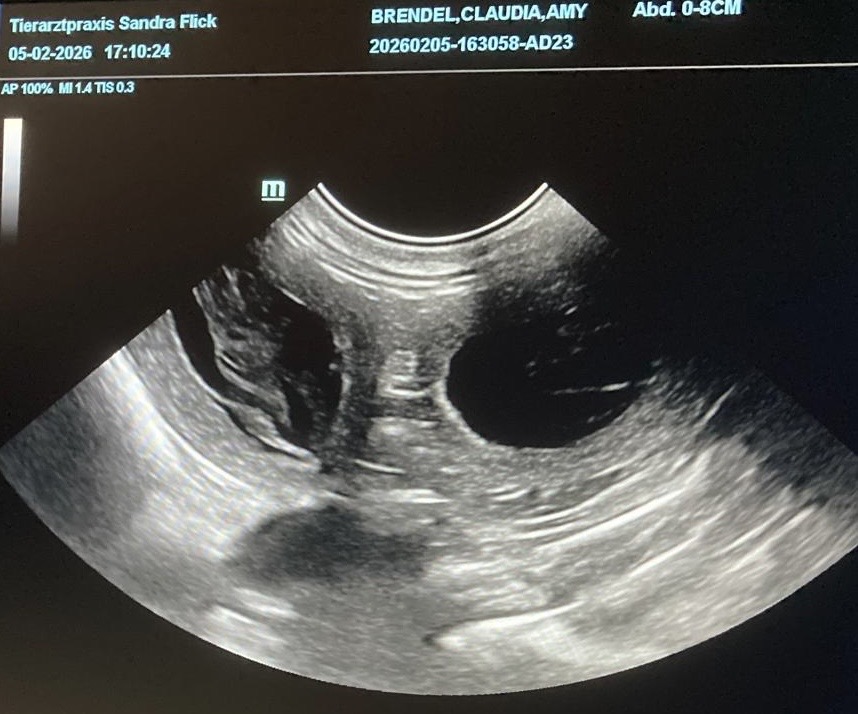

Amy ist tragend! Wir erwarten Welpen in schwarz-weiß um den 13. März 2026.

Der werdende Vater ist Zayn (Grace of Angel’s Home Kindred Spirit).